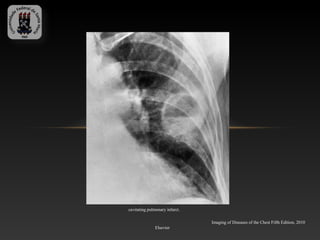

cavitating pulmonary infarct.

Imaging of Diseases of the Chest Fifth Edition, 2010

Elsevier